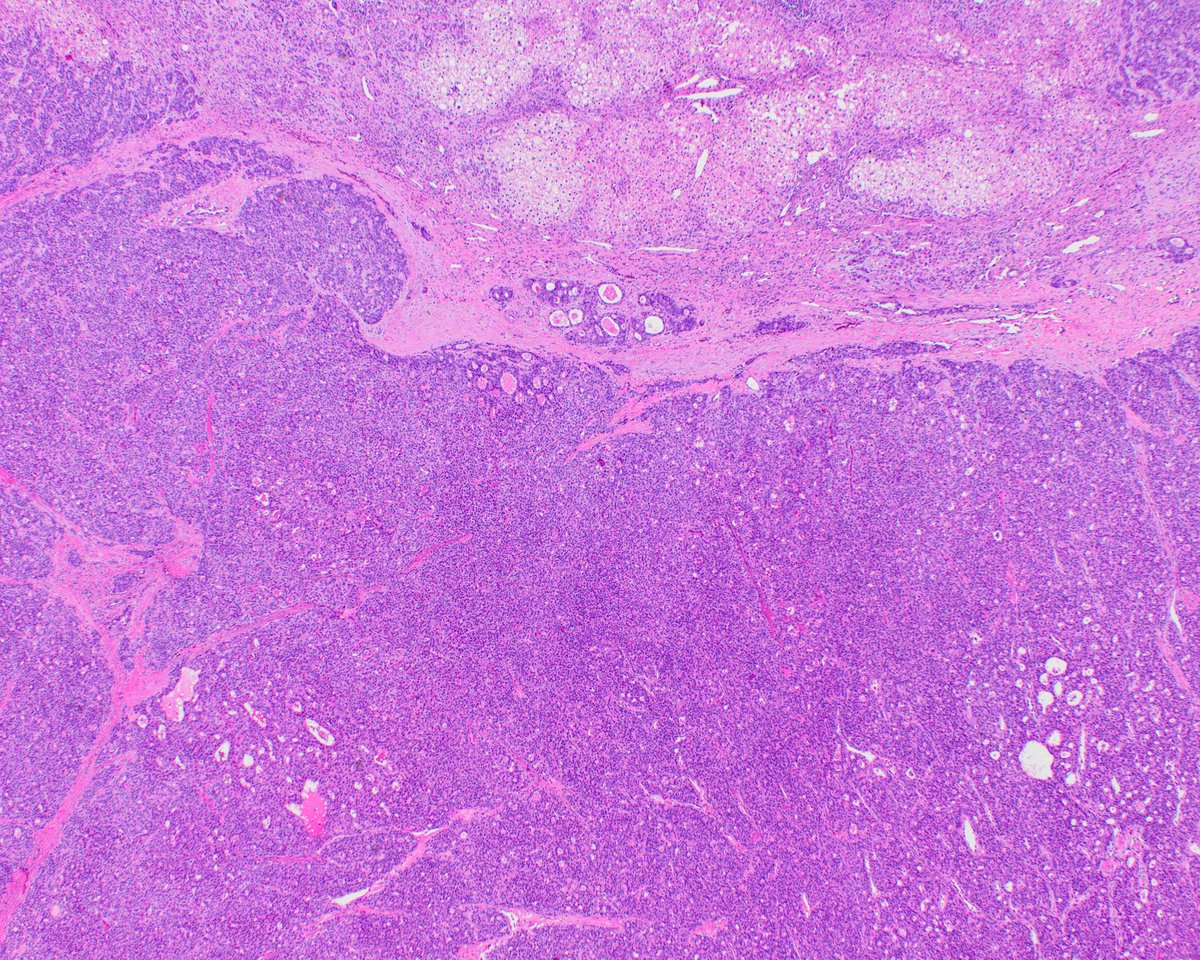

Granular/oncocytic lung carcinomas: what these are, and how they can cause diagnostic problems.

1/ Just out in @ModernPathology New study from our group: A distinct variant of aggressive lung carcinoma with peculiar pathologic features. We called these tumors “SAGA” (solid and granular adenocarcinoma) .. sorting them out was in fact a long and winding saga that led to some unexpected insights. 👇 modernpathology.org/article/S0893-… pubmed.ncbi.nlm.nih.gov/41580239/